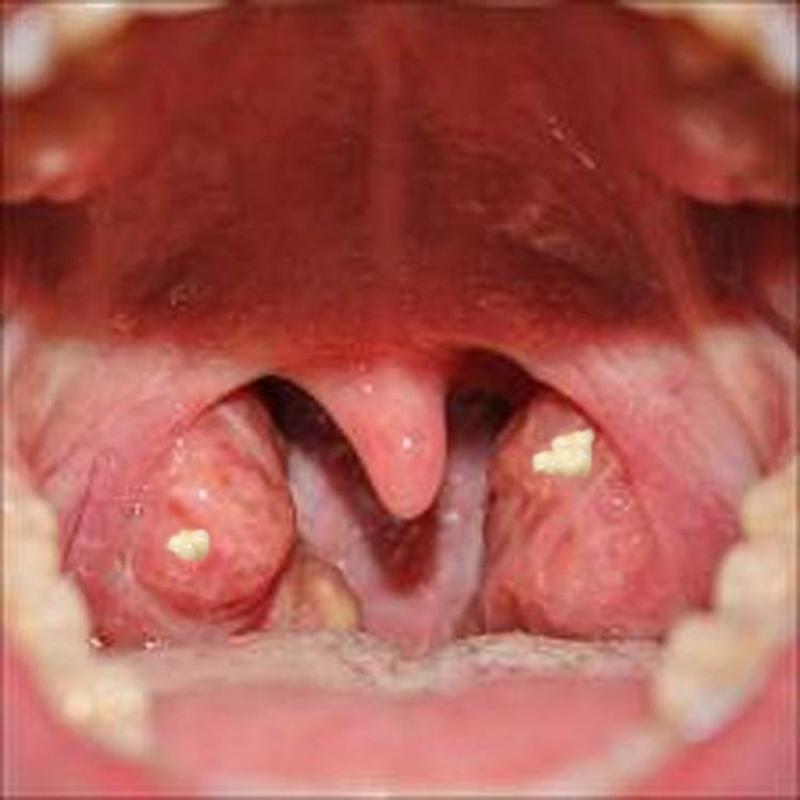

These Are Tonsil Stones

A large portion of people that have bad breath problems, in fact, have a problem with the so-called "tonsil stones." Tonsil stones are little white formations that appear on your tonsils. They are formed of various types of sulfur-producing bacteria.

The good news (if it can be called "good news" at all) about tonsil stones is that they are fairly easy to remove. In many cases, they can fall out on their own, or in other situations, you can remove them by mechanically scrubbing them off.

Sometimes Tonsil Stones Can Be Difficult to Detect

Although the tonsil stones depicted in these photos are easy to see, in many cases they can 'hide" on the other side of the tonsils. In that case, only a doctor can help you remove them. Ask your doctor to check your tonsil if you frequently suffer from bad breath.